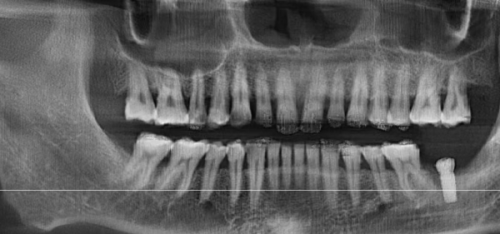

定期口腔检查与洁牙的重要性

即使日常护理做得再好,牙结石和隐蔽的牙病问题仍难以完全避免。建议每半年到一年进行一次口腔健康检查并做一次洁牙。洁牙可去除日常刷牙难以清理的牙结石和色素,预防牙龈炎和牙周病。医生还能通过检查早期发现潜在问题,及时给出处理建议。